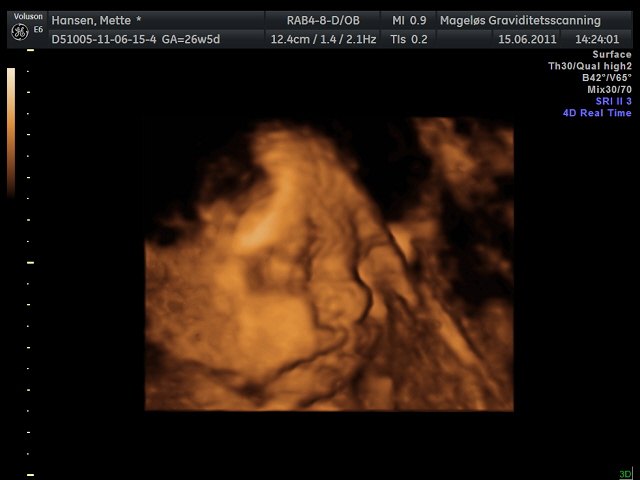

Så vil jeg da lige fortælle at jeg var til 3D scanning i dag med bassen Haha.. Han er en TOTAL livlig en, som bare ikk vil makke ret Han vendte og drejede sig HELE tiden.. Hihi.. Men han vejer omkring 1033g nu, og ALT så fint ud.. Lige bortset fra at hun synes at der var lidt meget fostervand ved tarmen, så hun ville gerne have at jeg skulle på sygehuset og finde ud af om det var noget alvorligt eller ej.. Men det mente hun ikk så for at der ikk er noget i vejen...

Men fik så set hans søde "ansigt" så meget man nu kan se.. Og mon ikk at vi da lige fandt 100% ud af det er en dreng haha.. Fik lige et billede en lille diller på.. Hahahaha.. Så fandt man da lige første billede til konfirmationen Men han elsker at have hans hænder ved ansigtet Til den sidste scanning havde han hånden deroppe og det havde han også næsten hele tiden den her gang Men nøjjj han er DEJLIG!!!